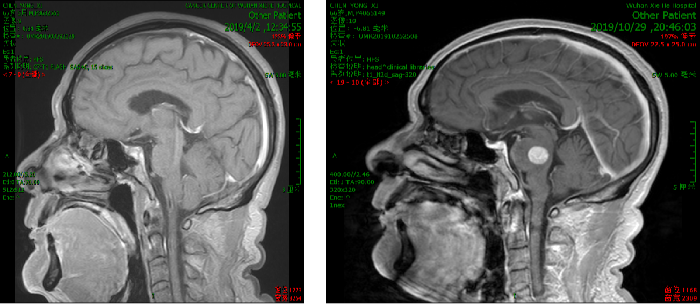

2019年10月患者出现头晕严重,不能下床独立行走,伴额头及右侧肢体麻木。

2019.10.18 当地医院头部MRI示:脑干区异常信号,约11mm*15mm,考虑转移瘤合并脑卒中。

脑部蛋氨酸PET示:脑桥结节,蛋氨酸代谢异常增高,SUVmax 4.51,考虑转移性恶性肿瘤。

影像科、神经内科会诊,考虑脑部病灶为肠癌转移病灶。

脑干转移病变,合并瘤卒中,周边水肿。

处理:2019.11.5至2019.11.10行射波刀放疗,DT 20GY/4F,同步替莫唑胺化疗。

10天后复查脑部CT提示病灶变化不明显,出血量无增加,水肿无增加。

处理:再次射波刀追加剂量,DT 20GY/4F,贝伐珠单抗200mg治疗一次。

效果:患者脸部麻木及右侧肢体麻木症状改善明显,肌力IV级,可独自行走。